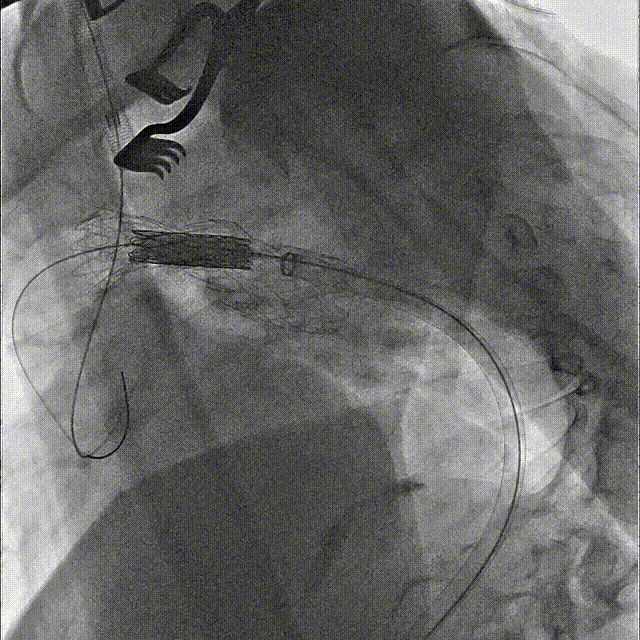

第一步、常规麻醉,消毒铺巾,分离显露左锁骨下动脉、左颈总动脉和左椎动脉备用。经右侧股动脉穿刺植入5F鞘,黄金标记猪尾导管升主动脉造影明确主动脉病变(图2)。

gore医疗怎么样「胸有乾坤」国际首例 微创杂交技术治疗巨大左锁骨下动脉瘤合并主动脉缩窄Larsen综合症患者_https://www.jmylbn.com_新闻资讯_第8张